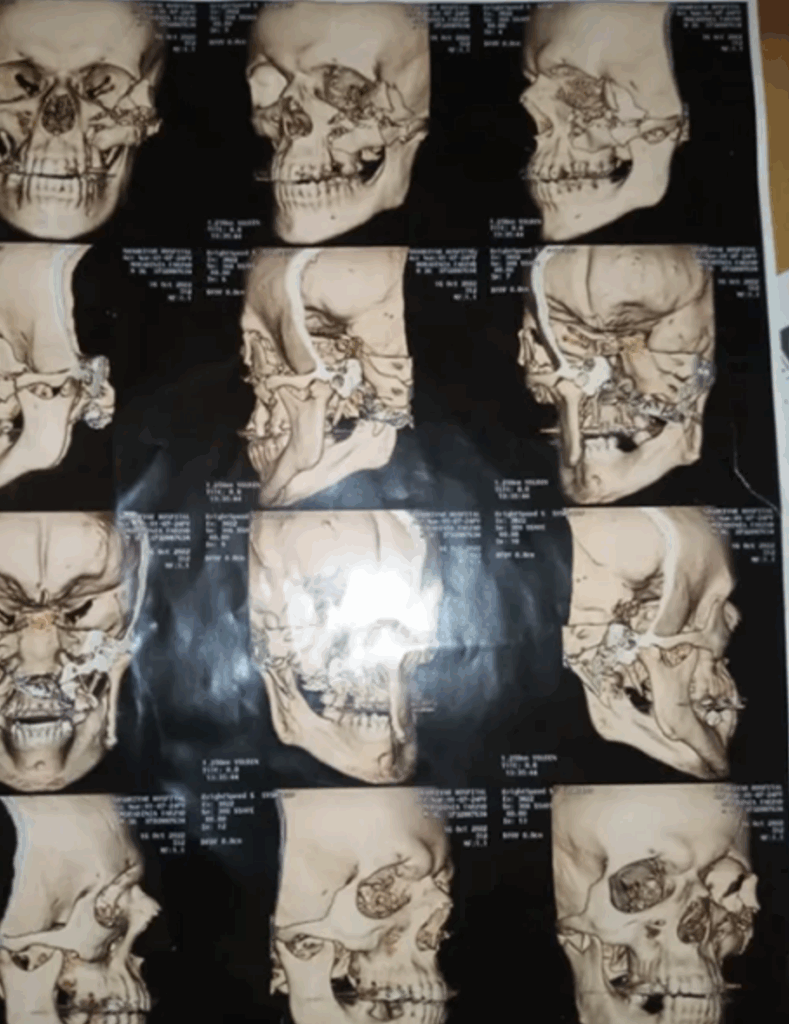

To prepare this report, the medical files of a number of individuals with eye injuries were shared with a global group of ophthalmology specialists. The results of their evaluations show that the pattern of eye injuries points to deliberate targeting. According to these specialists, the trauma caused by blindness is psychologically comparable to the experience of being diagnosed with cancer. This conclusion underscores the profound physical and psychological damages inflicted by this suppression tactic.

Furthermore, dozens of interviews were conducted with individuals injured during the protests, several of which are referenced in this report. Medical evidence was reviewed to corroborate the types of munitions used. Interviews with six physicians—including ophthalmologists and emergency medicine specialists in Tehran who had examined the gunshot wounds sustained by protestors—provided key insights regarding weapon type, shooting distance, and targeting practices. In addition, dozens of medical records from injured individuals were analyzed to assess the severity, nature, and location of their injuries. These findings were further reinforced by a specialized report prepared by IranWire in collaboration with health researcher Katherine Hignett, who reviewed and analyzed the medical files of 20 individuals affected during the 2022 protest suppression.[6]

Medical records of numerous victims who were shot in the head and eyes with shotgun projectiles demonstrate that the ammunition was discharged at close range. One such case is that of Hossein, a middle-aged man who lost both eyes and was permanently blinded. His medical file documents the presence of at least 300 pellets embedded around his eyes. At the time, he and his wife were attending the 40th-day memorial ceremony for Hadis Najafi, a young protester, in Karaj in Alborz Province. Witness accounts and medical evidence indicate that Hossein was shot with a shotgun while lying motionless on the ground as an act of submission.[94] Out of fear of reprisals by the Iranian government, he has chosen to remain anonymous.